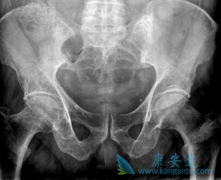

10月 19 多发性骨髓瘤的危害有哪些? 癌症 浏览次数:5335次 多发性骨髓瘤的发生很多时候是隐形的,因为这是一种慢性病,但是多发性骨髓瘤对患者身体的危害确实很大的。很多患者都不是很了解多发性骨髓瘤危害,下面就来看下多发性骨髓瘤的危害有哪些。多发性骨髓瘤的危害有哪些:骨痛骨痛是本病的主要症状之一。疼痛程度轻重不一,早期常是轻度的、暂时的,随着病程进展可以变为持续而严重。疼痛剧烈或突然加剧,常提示发生了病理性骨折。80例(64.0%)以骨痛为主诉,骨痛部位以腰骶部最常见(28.0%),其次为胸肋骨(27.0%),四肢长骨较少(9.0%),少数患者有肩关节或四肢关节痛... 查看更多